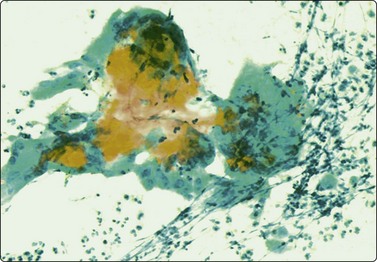

Merkel cell carcinoma (neuroendocrine carcinoma of skin) (Fig. 14.17, and see Fig. 5.23)61,62

image

Fig. 14.17 Merkel cell carcinoma

(A) Poorly cohesive cells; nuclear pleomorphism and some molding, scanty blue cytoplasm resembling lymphoid cells (MGG, HP); (B) Cellular smear of dispersed small cells with round, dark nuclei (Pap, HP); (C) Dot-like positive staining with CAM5.2 (immunostaining, HP).

Criteria for diagnosis

Cell-rich smears of mainly dispersed small neoplastic cells,

Fragile, scanty, blue (MGG) cytoplasm; high nuclear : cytoplasmic ratio; many stripped nuclei,

Clustered cells may show nuclear molding and rosette-like grouping,

Round or ovoid, mildly to moderately irregular hyperchromatic nuclei with inconspicuous nucleoli,

Mitoses frequent,

Lymphoid globules (lymphoglandular bodies) absent,

Dot-like paranuclear staining for cytokeratin; chromogranin usually positive.

Primary neuroendocrine carcinoma of skin is an uncommon neoplasm, mainly seen in elderly patients and most often in the head and neck. It is locally aggressive and often metastasizes to regional lymph nodes. Clinically and cytologically, Merkel cell tumor can be difficult to distinguish from non-Hodgkin lymphoma when it presents as lymphadenopathy without an obvious primary, as is often the case (see Chapter 5).

Page 379

Smears are usually highly cellular. The cells are mainly dispersed but some are clustered or form single files with nuclear molding and sometimes rosette-like groups. The main differential diagnoses are lymphoma and metastatic small cell carcinoma. Amelanotic melanoma may also be considered. The absence of lymphoid globules in the background and subtle differences in nuclear chromatin help in this distinction. Staining for CAM5.2, CK7 and CK20 demonstrates characteristic dot-like intracytoplasmic deposits in the tumor cells (Fig. 14.17C), and staining for neuroendocrine markers is usually positive. Electron microscopy shows well-demarcated whorls of cytoplasmic filaments.